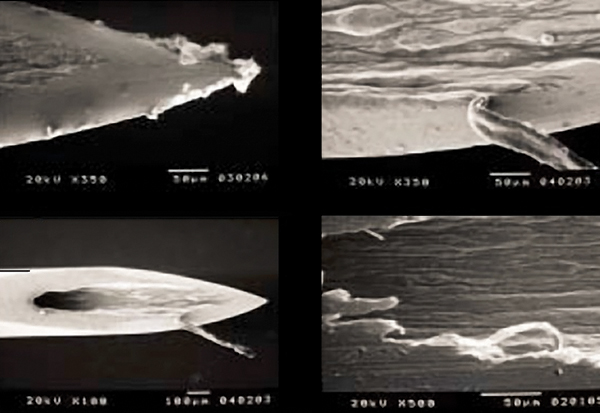

A needle with manufacturing defects is more likely to have existing, or easily created, barbing and splintering, which may result in issues with the penetration process of the needle, damage to soft and neuronal tissues, hemorrhage, or causing moderate to severe pain.34 During the manufacturing process, the cutting of the needle bevel can lead to irregularities in the stainless steel, which may result in these adverse outcomes (Figure 3). The creation of the irregularities is related to both the cutting process and the quality of steel being used.35

ISO (International Organization for Standardization) provides standards on the type of stainless steel as well as the minimum thickness of steel used in needle manufacturing. Because of organizations like ISO, manufacturing defects continue to decrease. However, defects still exist, especially on a microscopic level.35 In fact, a recent study evaluating the most commonly purchased needles found that the homogeneity in the metal alloys did not generally conform to international manufacturing guidelines.36 In addition, the authors concluded that a wide variation between applied standards exist and it appears that most manufacturers apply their own standards to the manufacturing process. Ultimately, the quality of material and the type of finish of the needle bevel is vital in decreasing the irregularities, which aids in decreasing barbing.34,35

Fig 3. Microscopic view of irregularities of unused dental needles (from: Sanchez DE, Fernandez RE. Microscopic assessment of dental needles. Guadalajara University. Used with permission.)